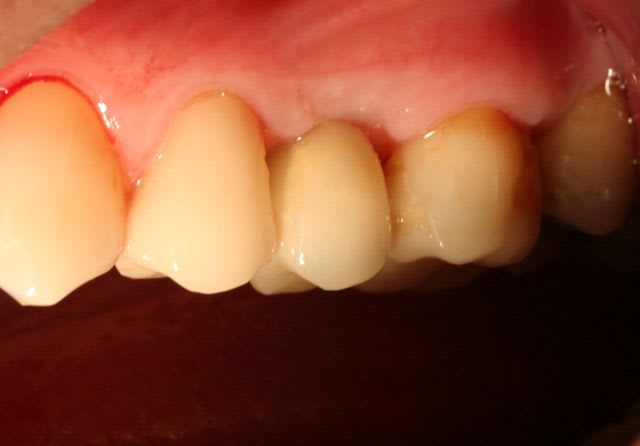

ci dessous quelques photos , schemas des implantations immédiates pour les incisives où tu peux creer une nouvelle alvéole grâce au foret jaune et condenseur spéciaux. Ainsi tu n as pas de collapse d alveoles en preservant le perioste.Si l espace entre l implant et le mur (ou paroi, je ne sais pas en francais?) buccal est supérieur à 1mm, j ajoute de la acide hyaluronique et quelques fois du collagène...

Les résultats sont enthousiasmants également après quelques années